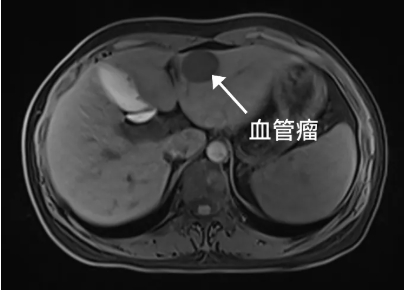

突然发现肝内长了一个

2.9cmm*2.7cm的血管瘤

“肝血管瘤名字里有个“瘤”,是不是就是得了肝癌的意思呀?”刘女士来到卢明柱主任专家门诊焦急地问。别怕,虽然名字里带有“瘤”字,但它并非恶性肿瘤,而是一种常见的肝脏良性肿瘤。“肝血管瘤,它是由肝脏内异常扩张的血管团组成。它通常生长缓慢,大多数情况下无症状,也不会恶变。通常在彩超体检中初步发现,进一步确诊往往需要增强CT或磁共振检查。但没有特效药物治疗。”卢明柱指出。